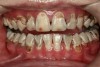

There are several advantages of using SDF in dental treatment. First, it showed an antimicrobial activity against mono-species, dual-species, and multi-species cariogenic biofilm.14-16 Silver ions are bactericidal metal cations that inhibit biofilm formation.17 Studies have indicated that silver interacts with sulfhydryl groups of proteins and DNA, thus altering hydrogen bonding and inhibiting respiratory processes, DNA unwinding, cell-wall synthesis, and cell division.18 At the macro level, these interactions affect bacterial killing and inhibit biofilm formation.17 Second, fluoride promotes caries lesion remineralization. Fluoride has been indicated to react with hydroxyapatite and generate calcium fluoride, which is a reservoir of fluoride, and facilitate further remineralization.19 An ex vivo study reported surface microhardness of the surface layer of the arrested caries after SDF applications was comparable with the unaffected sound dentin20 (Figure 1 and Figure 2). This is consistent with another study, in which a high remineralized zone was observed on the surface of arrested caries from exfoliated teeth with SDF treatment21 (Figure 3 and Figure 4). Third, its application procedures are simple and do not require injection or drilling, and the treatment does not involve expensive support infrastructure equipment such as piped water and electricity. The simplicity of the treatment is conducive to treating caries in apprehensive young children who may have intense dental fear, uncooperative patients with special needs, or elderly patients who have difficulty adapting to traditional dental care. It also allows trained workers to deliver the treatment to people who live in the area but who may not be able to easily access dental service.22 Patient compliance and satisfaction is often good when the patient is provided a clear explanation of the treatment outcome.23,24 Finally, the cost of SDF treatment is low and should be affordable in most communities.